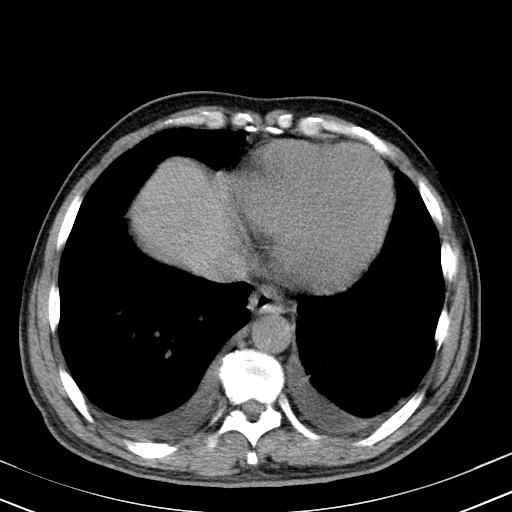

以下是引用zxl51642在2010-3-21 17:06:00的发言:[br]右下中心型肺癌并阻塞性肺炎/不张,纵膈淋巴结肿大,右侧大量胸腔积液,左侧少量胸腔积液,少量腹水。建议纤维支气管镜进一步检查。